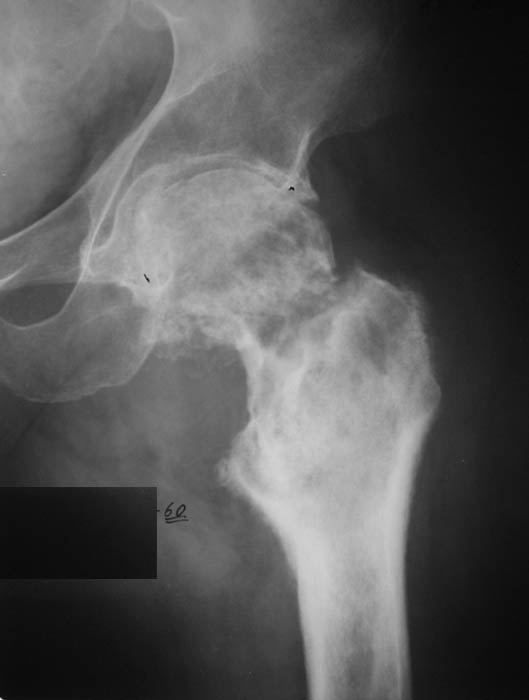

И снова вопрос по эндопротезированию: Пациенту 51 год. Болен с 2000 г, когда отметил умеренные, нараостающие боли в в/3 левого бедра, прогрессирующую контрактуру лев Т/Б сустава.

05.12.04 после падения на бедро боли резко усилились, нога стала неопорной. На рентгенограмме обнаружен патологический перелом шейки бедренной кости. Обследован в отделении костной онкологии. Результат биопсии: асептический некроз проксимального отдела бедренной кости. Вопрос: выбор технологии эндопротезирования - цементная или бесцементная версия. Заранее благодарю! С уважением,А.В.Владзимирский

Учитывая приличную форму вертлужной впадины и возраст

пациента, мы бы у себя поставили чашку Spotorno или

аналогичную (expanded). Только не стоит сильно выбирать субхондральный слой.

Про ножку трудно сказать, снимки очень короткие.

Проксимальный отдел бедра не виден достаточно на представленных рентгенограммах; но то, что видно, как раз наводит на мысли о цементной фиксации - цилиндрический канал, измененный calcar, кистозные изменения в области большого вертела и т.д.

Evgueny Tchekashkine 01 Февраль 2005, 04:15

Как то очень подозрительно выглядит проксимальный отдел бедра для такого очень простого гистологического заключения. Вы уверены, что гистология настолько благополучна и в каком варианте она выполнялась: пункционная или открытая с забором костного блока? Не уверен на все сто , но область проксимального отдела бедра - одно из излюбленных мест для гигантоклеточной опухоли, которая зачастую озлакочествляется (имел два подобных наблюдения). Из своей практики могу сказать, что, к сожалению, информативность пункционной биопсии не сравнима с открытой техникой. Поэтому прежде чем решать цементный или бесцементный протез использовать, я бы повторил биопсию в сочетании со сканированием скелета, сывороточная щелочная фосфатаза, кальций, фосфор сыворотки, СОЭ, С- реактивный белок,

Soglasen s Евгений И Чекашкин, proximal Femur does not look right. Sarcoma? Pagets, Osteomyelitis?. Technicality of the implantaion will be dependent upon underlying pathology, and the surgeon's level of comfort.

Ацетабулум как-то странно выглядит, с дыркой.

Действительно, проксимальный отдел бедра выглядит подозрительно. По-моему напоминает болезнь Педжета. Кстати, гистологическое заключение в таком случае часто звучит как "хроническое воспаление", "асептический некроз с элементами лейкоцитарной инфильтрации" и т.п. Далеко не все патоморфологи имеют достаточный опыт для дифференцировки костной патологии.